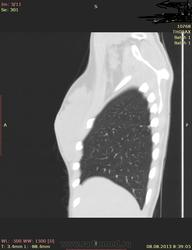

Здраствуйте, коллеги. Нужна ваша помощь молодая девушка 21 г. в течении 2-х лет беспокоит субфибрильная температура, период.гол. боль. В прошлом году сделала ОГК зак: туберкулема. Ей сказали что она перенесла тбс. на ногах, лечение не принимала. Сдавала все анализы без изменении.Родная сестра 3 года назад перенесла тбс.

Туберкулёма в 6-ке.

Распада не вижу, очагов отсева тоже. Контроль и к фтизиатру.

По показанным изображениям данных за активность нет, но без дайкома однозначно не сказать. Посмотрите в MIP при толщине среза 4-6 мм очаги. Если у девушки иммунодефицит любого генеза, то картина даже через несколько дней может кардинально поменяться, так что в любом случае конс.фтизиатра.

Справа в С6 - неправильной округлой формы образование повышенной интенсивности с включениями извести. Данное образование связано с корнем лёгкого бронхо-сосудистой "дорожкой". Рекомендовано анализ мокроты на МБТ!